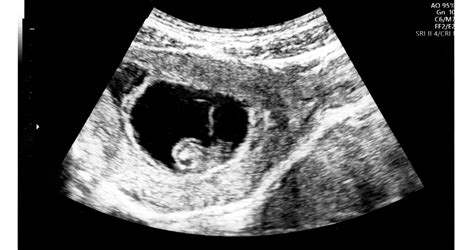

A rendszeres nőgyógyászati szűrés kulcsfontosságú a nők egészségének megőrzésében. Sok nőgyógyászati probléma kezdetben tünetmentes lehet, így a korai felismerés elengedhetetlen a hatékony kezeléshez. Az ultrahang vizsgálat, amely Dr. Lengyel Mária rendelésén a vizsgálatok részét képezi, fontos eszköze a magzati fejlődés követésének és a nőgyógyászati eltérések kimutatásának.

A 6. hét után már általában hallható a magzati szívhang ultrahangvizsgálaton. Fontos tudni, hogy a 12. hétig 6 százalék esély van a magzat halálára, ezért a terhesgondozás során kiemelt figyelmet kell fordítani a magzat egészségére.